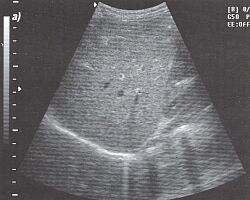

4.Техника получения продольного среза печени. Плотно устанавливаем датчик на кожу под мечевидный отросток и направляем его вверх (рис. 7), затем смещаем в латеральном направлении (параллельно исходной позиции) так, чтобы осмотреть всю печень (рис. 8). Этот срез идеален для исследования левой доли печени.

|